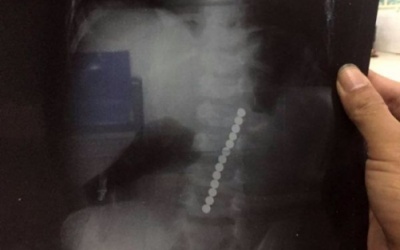

Thấy bé Sang có biểu hiện nôn ói, nóng sốt nên gia đình đưa đến bệnh viện, sau khi chụp X-Quang, bác sỹ và gia đình tá hỏa phát hiện 13 viên bi xếp thành dãy dài trong dạ dày của cháu.

Liên tiếp các trường hợp trẻ vô tình nuốt phải dị vật khiến dị vật mắc tại đường tiêu hóa gây nguy hiểm đến tính mạng phải nhập viện cấp cứu là lời cảnh báo cha mẹ và...